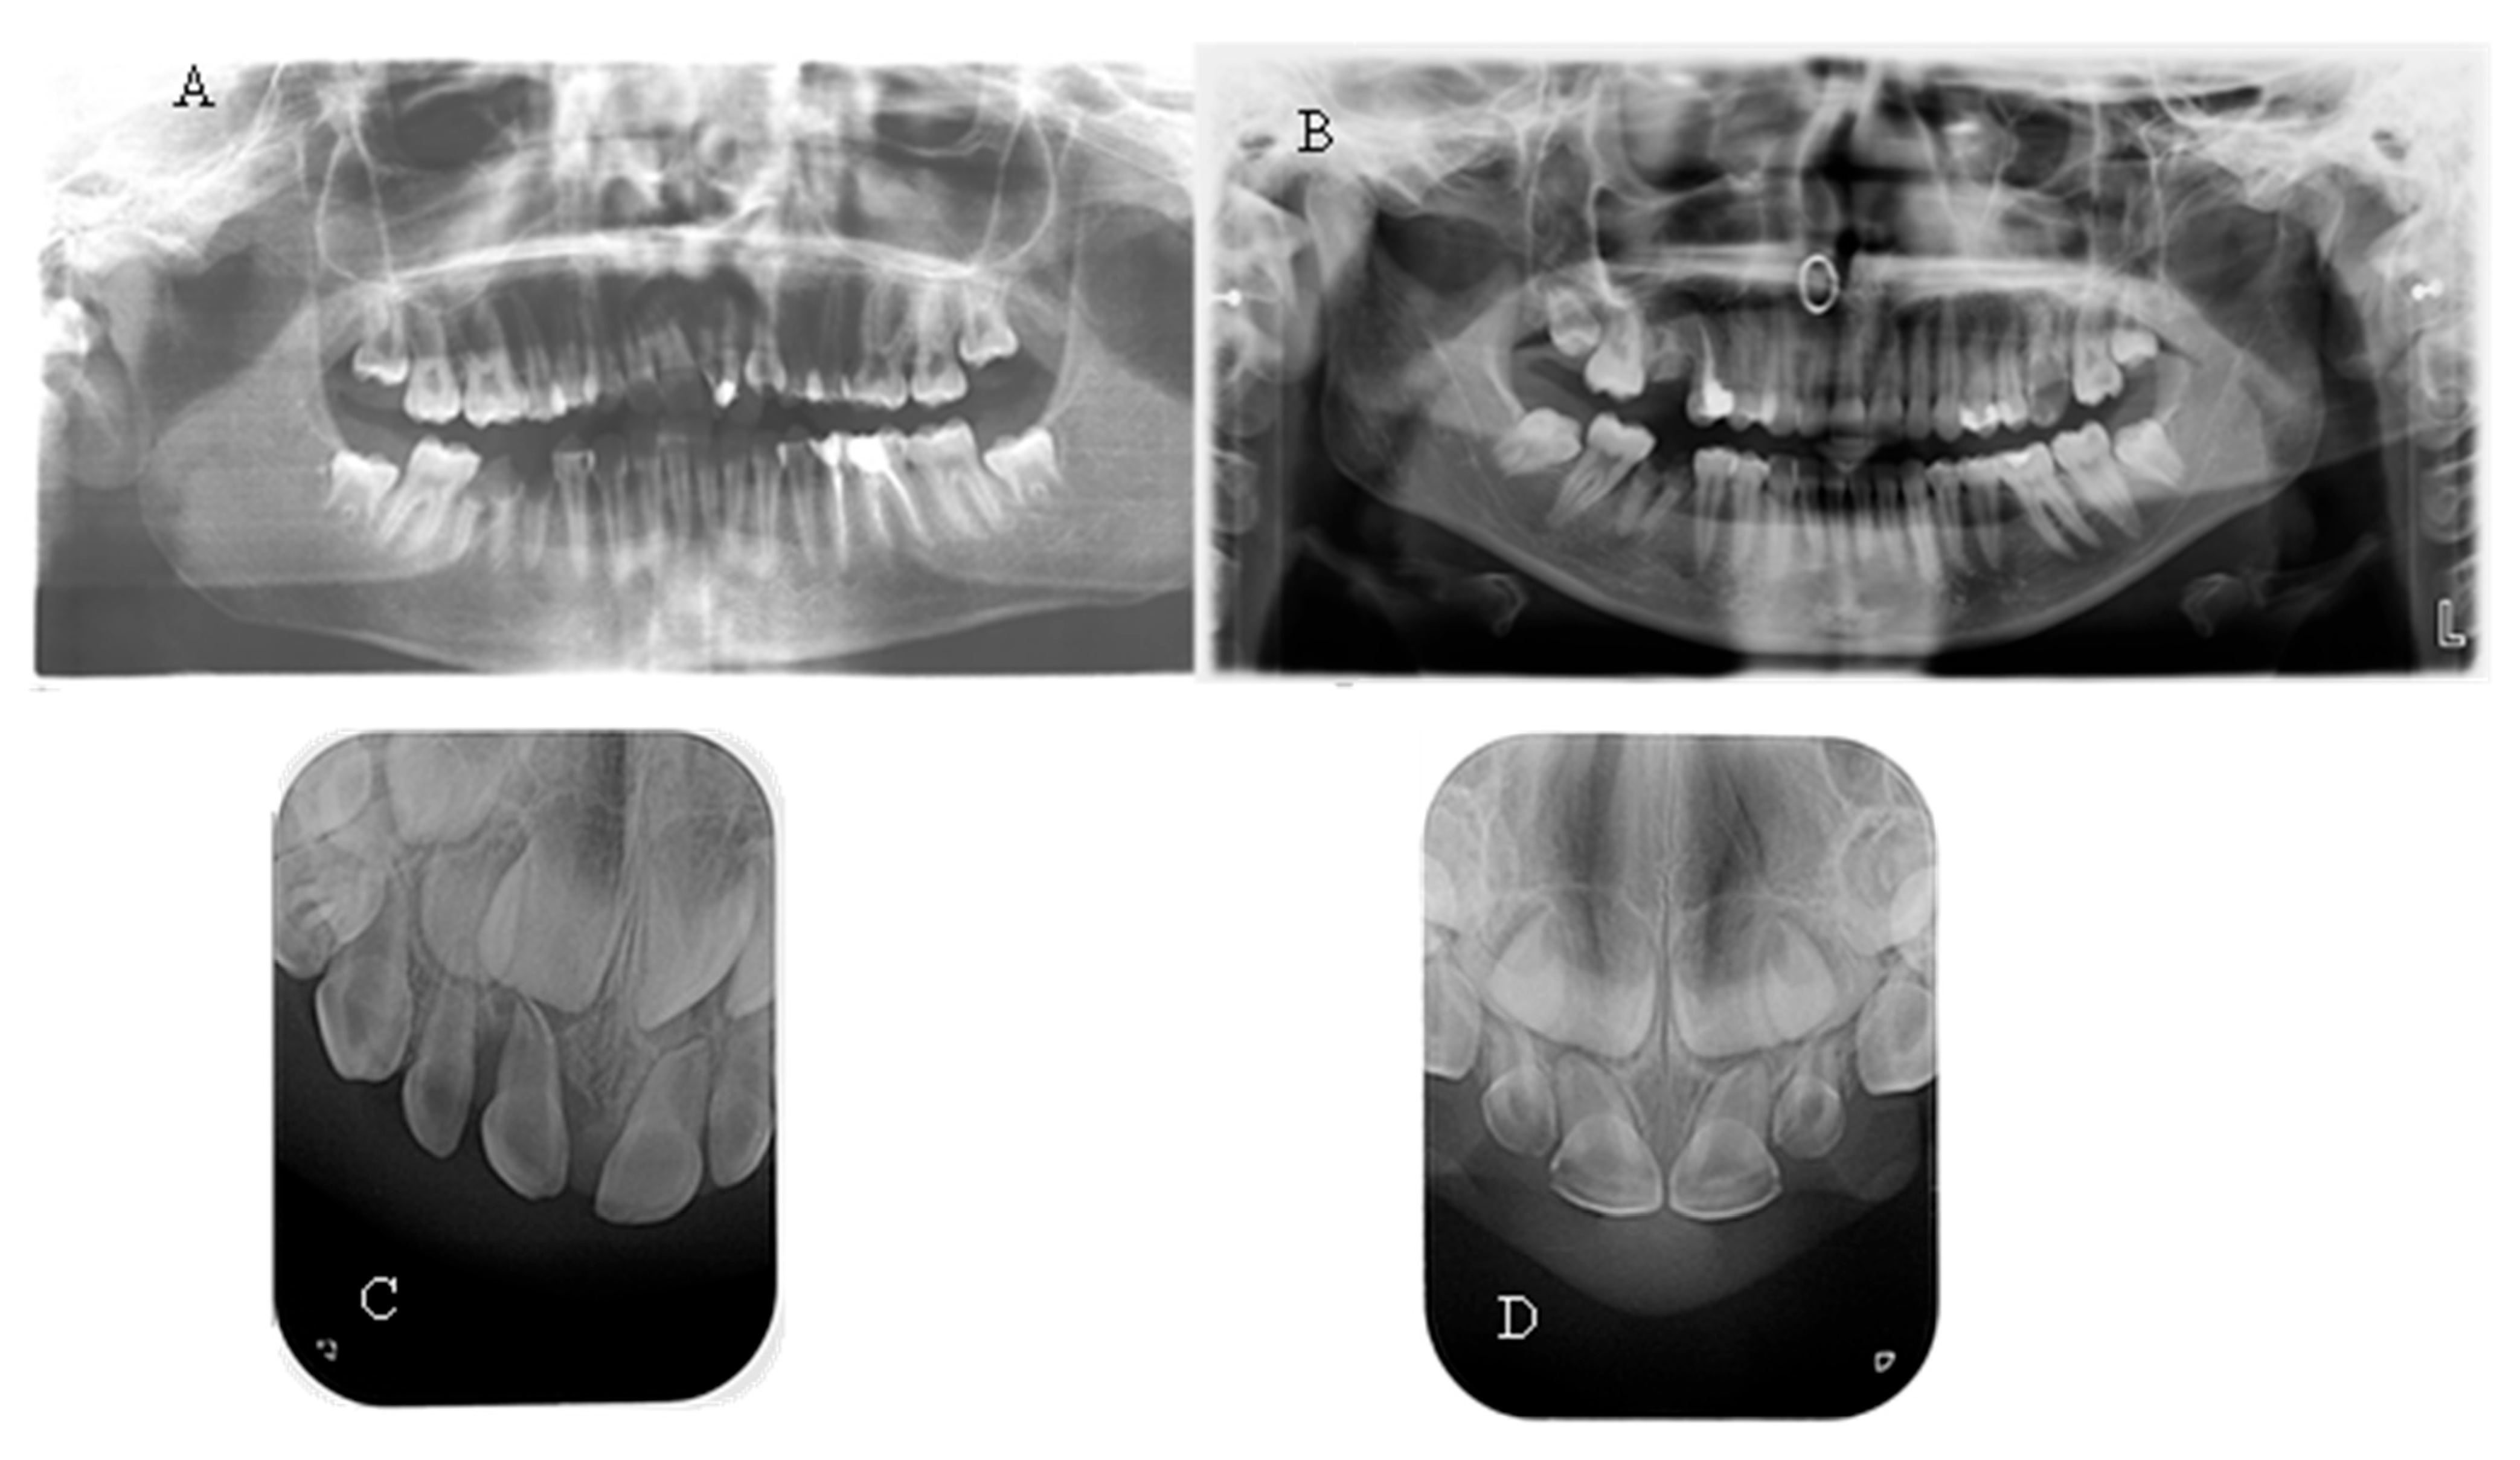

The spontaneous endodontic infections described in the literature were found in two of the examined children (18.8%). The first child, a 17-year-old girl, reported pain and swelling in the lower anterior region about a year ago, which was treated with antibiotics since no apparent cause was found after a visit to the dentist. There were no complaints at the time of the examination; the dentition was intact, and the mucosa and gingiva were normal. When performing a cold test, tooth 41 did not react. On a periapical X-ray, a large periapical lesion was observed in tooth 41 (Figure 4). The unusual anatomy of the coronal pulp of the anterior teeth, which had several pulp horns, extended towards the incisal edge, was striking. The girl had previously been treated with burosumab, but the treatment was interrupted at the request of the family and is about to be restarted.

The second child, 2.5 years old, was brought in by the mother, who had noticed a fistula in the lower frontal area. The mother reported no history of trauma. Upon clinical examination, a vestibular fistula was observed in the apical region of tooth 81, which appeared intact. The sectional radiograph revealed periapical radiolucency and delayed root development of tooth 81 compared with tooth 71, indicating pulp necrosis (Figure 4). The radiograph also showed a thin layer of dentin on all the frontal teeth, particularly in the root area, along with wide pulp chambers and root canals. The child has not yet begun treatment for the general condition.

Figure 4. (A) Intraoral image of a 17-year-old girl with XLH; (B) Intraoral X-ray of the same girl with visible necrosis of an anterior teeth without previous trauma history; (C) Intraoral X-ray of a 2.5-year-old girl with XLH. Thinner radicular dentin is clearly visible.